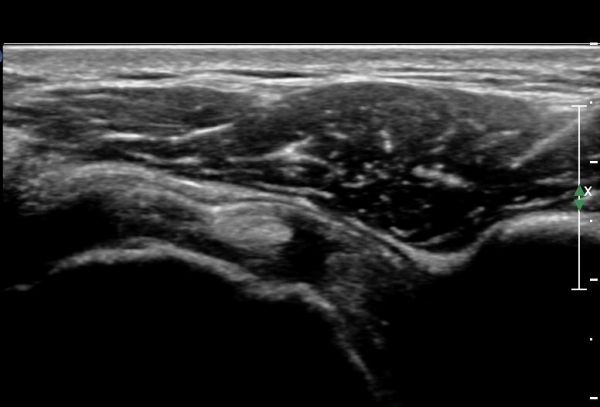

¿À±¸µ¹±â°ßºÀÀδë Á¾´Ü¸é°Ë»ç¿¡¼­ ÀÎ´ë ½ÉÃþ¿¡ ¼ö¾×Àú·ù°¡ °üÂûµÊ(»çÁø 1, 2)

ÀÌ´Â Ãæµ¹ÁõÈıºÀ» ¾Ï½ÃÇÏ´Â ¼Ò°ßÀÓ.